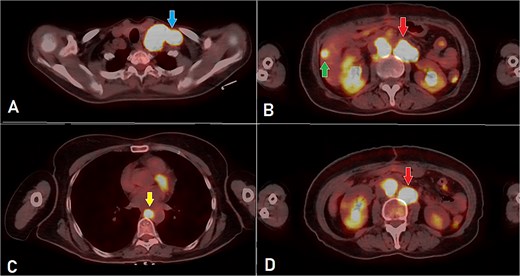

A computed tomography (CT) scan was performed, and the patient underwent a right hemicolectomy using a laparoscopic-assisted approach, with en bloc resection of the tumor and lymphadenectomy. The procedure was uneventful, with no intraoperative complications, and the patient had an unremarkable immediate postoperative recovery. The staging was determined as T4bN2bMx. Further imaging revealed enlarged mediastinal, supraclavicular, and retroperitoneal lymph nodes, with a solitary liver lesion (Fig. 1). A biopsy from the supraclavicular node indicated moderately differentiated adenocarcinoma of gastrointestinal origin. Molecular profiling showed wild-type RAS, intact MSI, mutant BRAF, and HER2 negative. The patient was started on capecitabine-oxaliplatin (CapeOX) with bevacizumab and completed 11 cycles with a marked clinical and radiological response (Fig. 2).

PET-CT scan at the corresponding cuts to Fig. 1 showing great metabolic and morphological regression regarding the previously seen (A) supraclavicular lymph nodes (arrow); (B) retroperitoneal lymph nodes (inferiorly pointing arrow) and hepatic lesion (superiorly pointing arrow); (C) mediastinal (para-oesophageal – station VIII) lymph node (arrow); and (D) retroperitoneal lymph nodes (arrow).